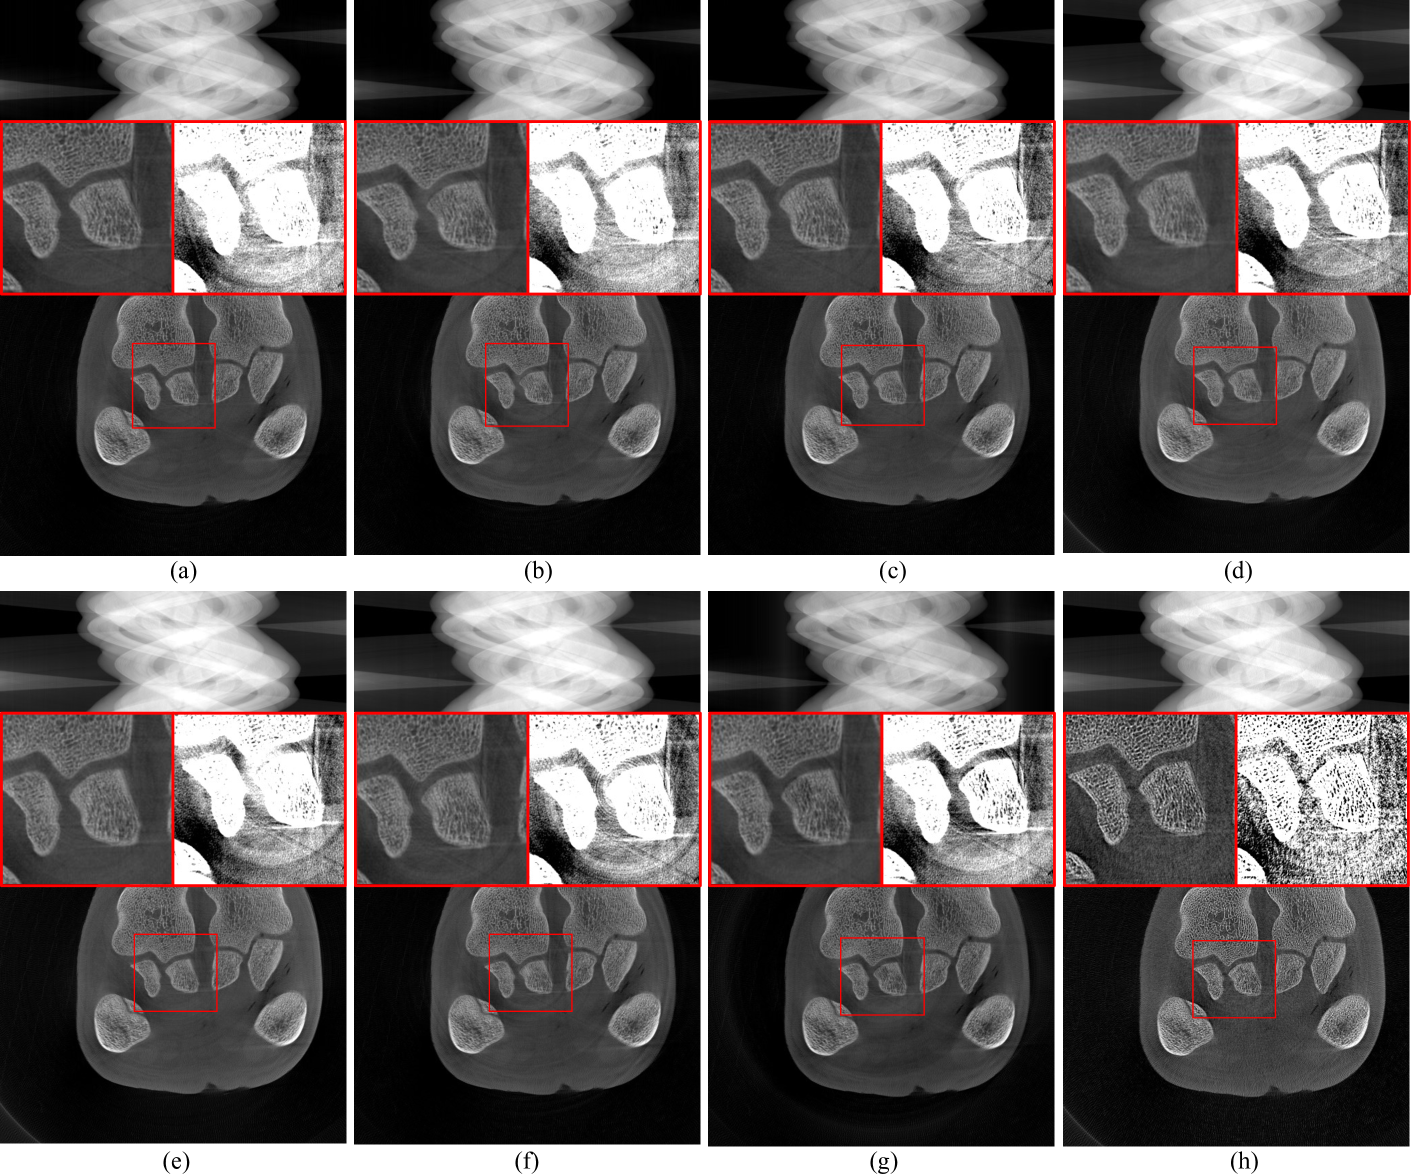

Figure 10: Comparison experiments with real data. (a) Combination method. (b) Method from [34]. (c) Method from [21]. (d) Normalization method. (e) FFT method. (f) W-FFT method. (g) Regularization method. (h) Proposed method. The display range is [0, 3.144] for the sinograms and [0, 0.010] for the CT images. The zoom-in view on the left shows [0, 0.010], and on the right, it shows [0.0016, 0.003].

In this section, a real data experiment was conducted using a 120 kV X-ray source (Libra13UlNE, iRay, China) to generate X-rays. The detector used was a Flat-Panel Photon Counting Detector (EIGER2, DECTRIS, Switzerland). The scanned sample was a fresh pork trotter. Fig. 8 shows the PCD-CT system and the scanned sample. The scanning configuration was consistent with that of the simulated data experiments. Fig. 9 shows the sinogram data collected during the experiment. The first row of Fig. 9 (a) shows the reference sinogram, where black stripes caused by the gaps between the FPCD panels can be observed. Most existing stripe artifact removal methods struggle to handle artifacts caused by defective pixels, such as these black gaps. To comprehensively evaluate the performance of the proposed method, linear interpolation was used to preprocess these black gaps to evaluate the performance of the proposed method comprehensively. The first row of Fig. 9 (b) shows the preprocessed sinogram. To ensure fairness in the comparison experiments, the relevant parameters of the compared methods were fine-tuned from their default settings to achieve optimal stripe artifact removal performance.

Figures 10 (a), (b), (c), and (h) show the results of stripe artifact removal from the sinogram containing black gaps in Fig. 9 (a). All methods successfully removed the black stripes and reduced other stripe artifacts. The results of the combination method [14] in Fig. 10 (a) demonstrate its effectiveness in removing stripe artifacts. The overall image is clear, and details are well-preserved. However, in the local zoomed-in regions, some ring artifacts remain. Fig. 10 (b) shows the result after applying flat-field correction and linear interpolation for defective pixels (black gaps), followed by TV-L1subscript𝐿1L_{1}italic_L start_POSTSUBSCRIPT 1 end_POSTSUBSCRIPT aG filtering. The results indicate that while details are well preserved, noticeable ring artifacts remain in the local zoomed-in regions. Fig. 10 (c) uses a dual-domain regularization iterative method. The reconstructed results still show slight ring artifacts in the local zoomed-in regions. Fig. 10 (h) presents the results of the proposed method, where defective pixels (those at the black gaps) were not involved in the neural network training. These defective pixel values were predicted by the network 𝐅𝚯subscript𝐅𝚯\mathbf{F}_{\mathbf{\Theta}}bold_F start_POSTSUBSCRIPT bold_Θ end_POSTSUBSCRIPT. The proposed method can maintain image continuity while filling gaps and effectively controlling ring artifacts. Figures 10 (d) to (g) show the experiments on stripe artifact removal from the sinogram after linear interpolation of the black gaps in Fig. 9 (b). Although these methods improved the quality of the reconstructed images and reduced ring artifacts to some extent, residual ring artifacts can still be observed in the local zoomed-in regions. The proposed method in Fig. 10 (f) best preserves image continuity and reduces ring artifacts.

In summary, when comparing the methods in Fig. 10, the method in Fig. 10 (a) is relatively complex, achieving good stripe artifact removal results but still leaving slight ring artifacts. The methods in Fig. 10 (b) and Fig. 10 (c) require extensive parameter tuning to achieve satisfactory results. Methods in Fig. 10 (d) to Fig. 10 (g) leave some residual ring artifacts. Fig. 10 (h) provides the best ring artifact removal and the clearest reconstructed image. Comparative analysis shows that the proposed method effectively removes ring artifacts, whereas other methods leave varying degrees of ring traces in the reconstructed images.